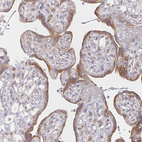

Immunohistochemistry analysis in human epididymis and skeletal muscle tissues using HPA048957 antibody. Corresponding DERL2 RNA-seq data are presented for the same tissues.